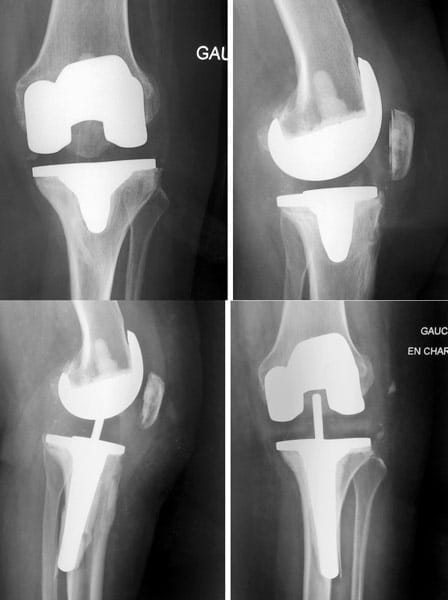

Douleur + raideur + boiterie. Homme 75 ans, opéré du ligament croisé antérieur 40 ans auparavant. On propose une prothèse totale du genou. Rééducation immédiate, récupération en 4 mois sauf complication.

Prothèse totale du genou NexGen (société Zimmer) à glissement, cimentée au fémur, au tibia et à la rotule, plateau polyéthylène fixe, postéro-stabilisée.

Femme de 88 ans, opérée par prothèse totale du genou NexGen à droite il y a 19 ans et à gauche il y a 18 ans.

Aucune douleur, aucune usure.

La courbe de survie de la prothèse NexGen dans les registres Australien et Anglais est de 98% à 11 ans de recul.